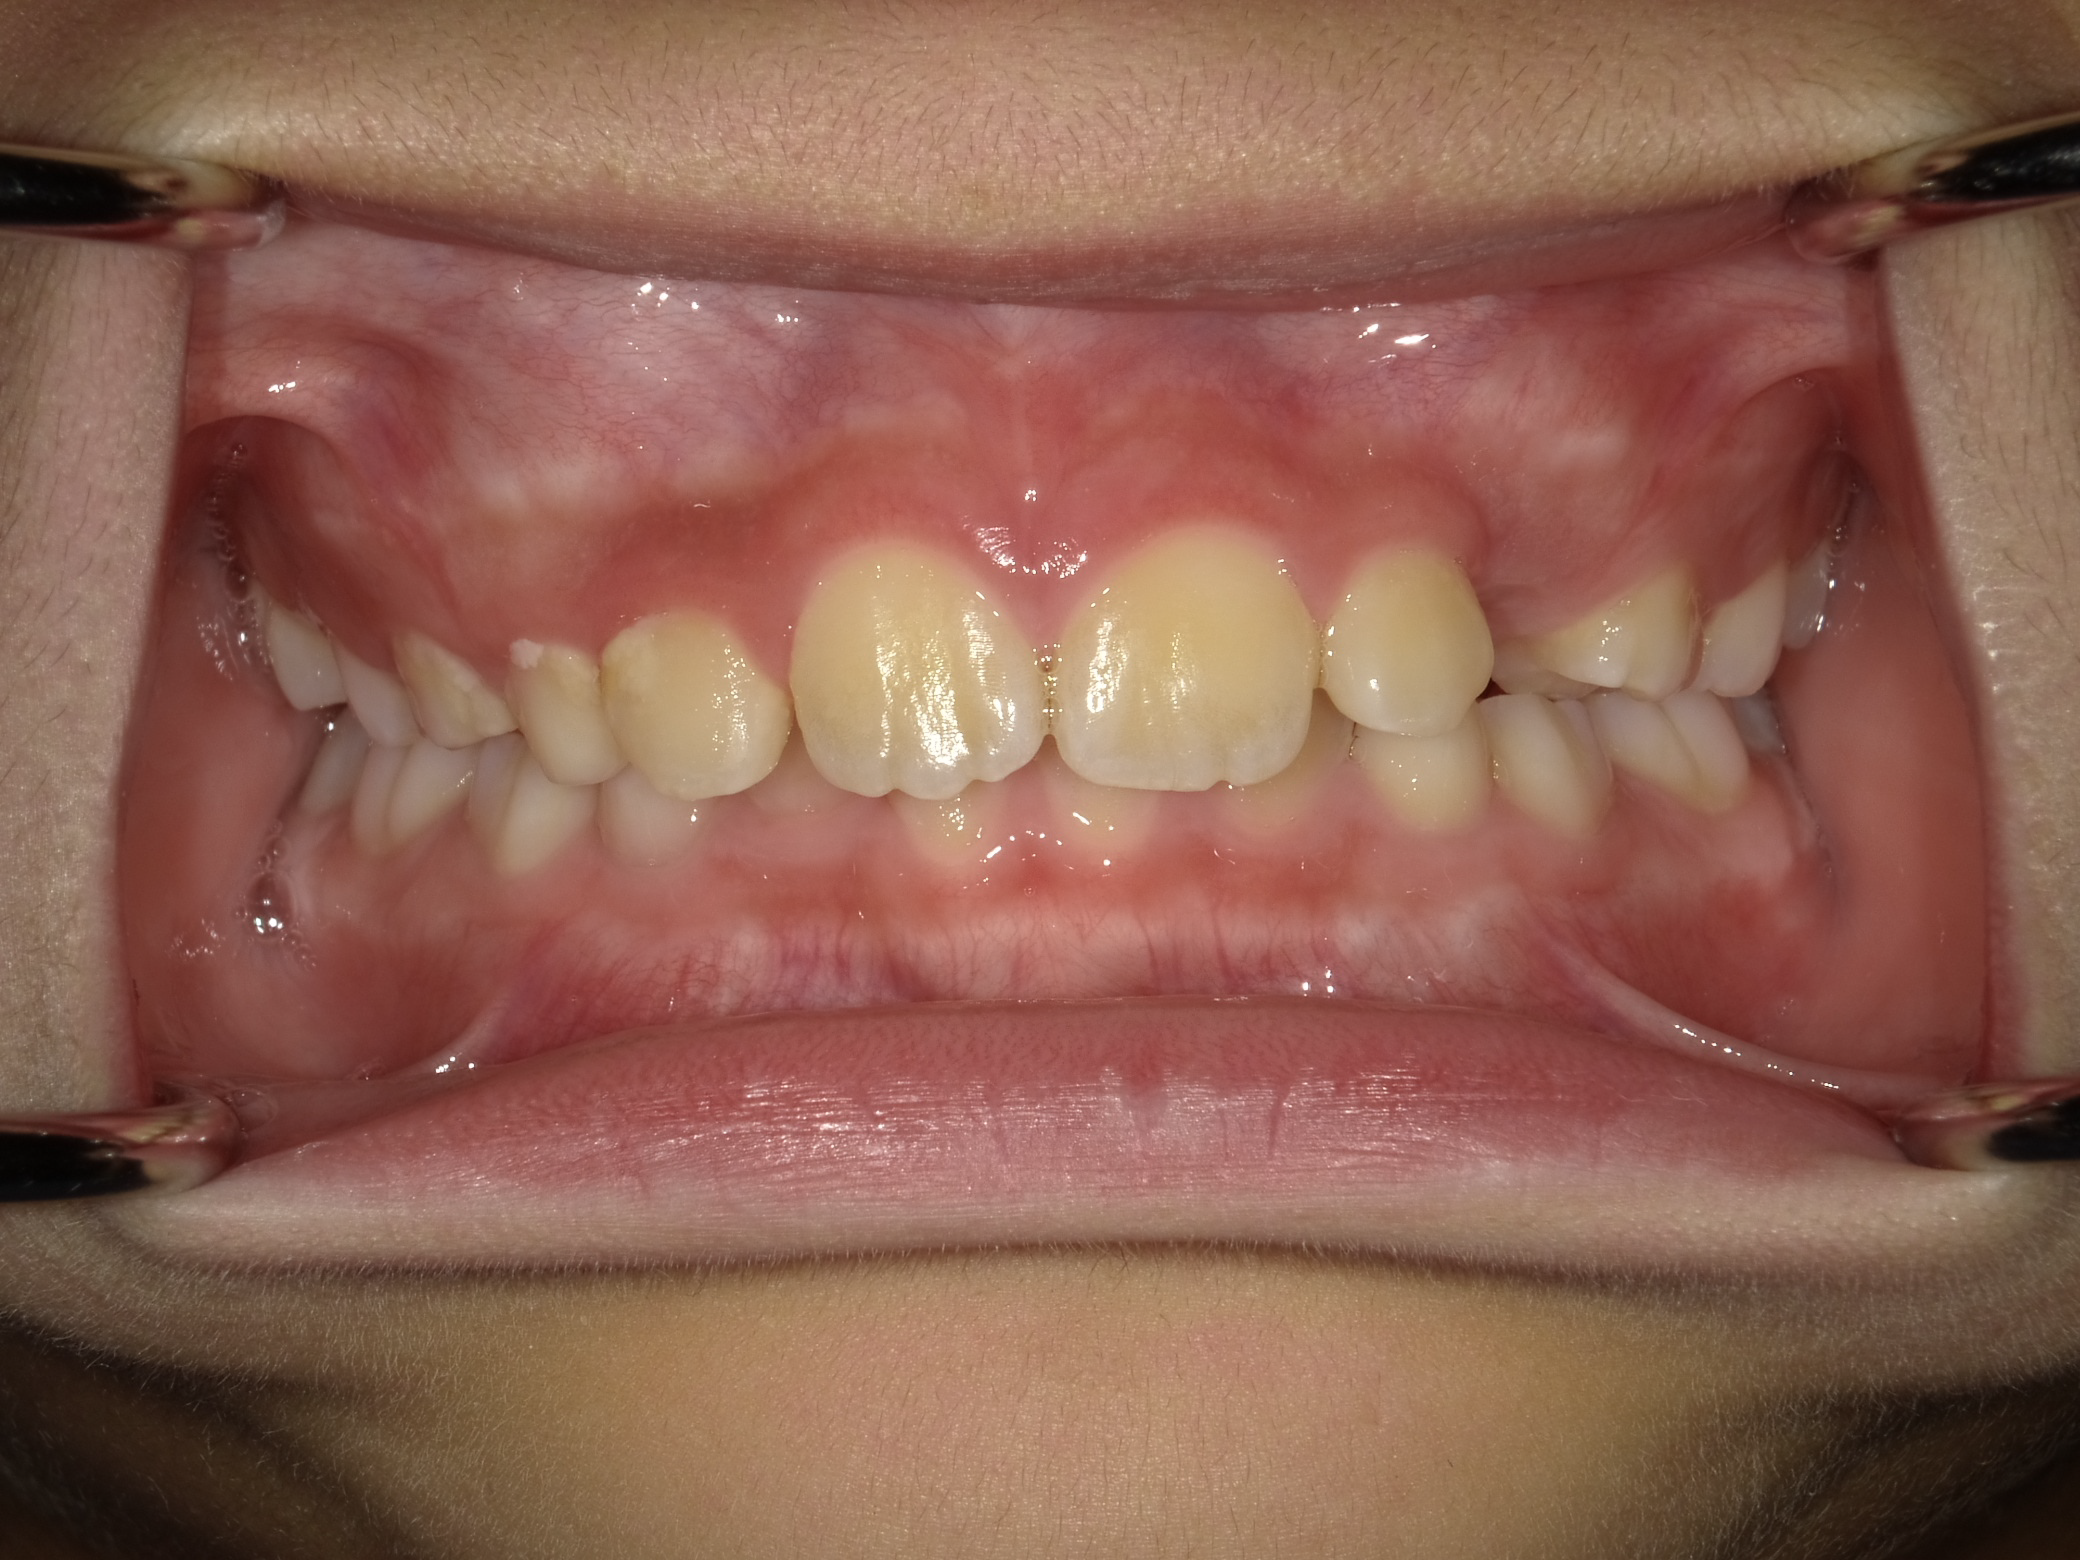

1期矯正の経過

時間はかかりますが、だいぶ凸凹が改善してきました。しかしまだ正面か見ると下の歯が見えません。

今回は上の歯が出過ぎているというより、下の顎は引っ込みすぎていると診断し、下顎を前に誘導する装置を使用します。

装置使用前後の比較

前歯に若干の凸凹はありますが、あとは2期治療で簡単に改善可能です。